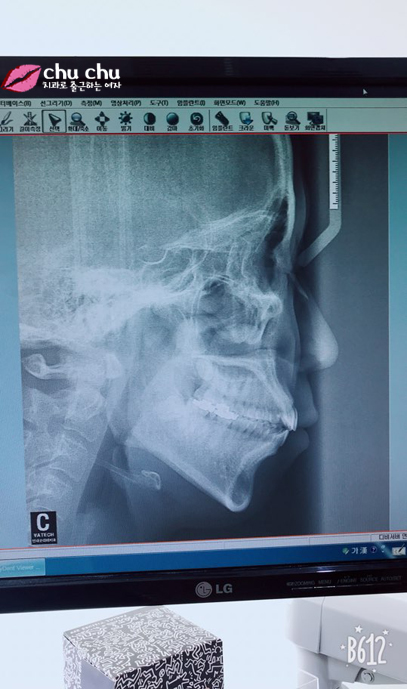

![[ 연세굿데이 교정 ] 우리 직원이 달라졌어요 - 돌출입치아교정 start 관련 이미지 1](https://pub-9f2bb3498faf4d1d8714b41df24753e3.r2.dev/content/clinics/archive/5hurea2jnb/naver_blog/eunkyo3370/assets/by_hash/d3af2105fcca6b1770a700bb50b7ddfe4f36dd14c8fab89ebf45b9079059a6c7.jpg)

교정하기 전 옆모습인데 평소에 돌출입으로 고민이 있으셨대요 ;;

근데 치과를 다니면서도 꽤 오랜시간 교정을 할까 말까 고민은 했대요.

그럼 현재 치아 상태는 어떻고 돌출입치아교정은 어떻게 계획을 잡고 들어갈까요?

원장님께 직접 여쭤봤습니다.

전형적인 돌출입이지만 이가 고르지 않은건 심하지 않은 편입니다. 3~4개월 정도 가지런히 하는 기간을 거치고 그 이후에 돌출입을 집어 넣게 됩니다.